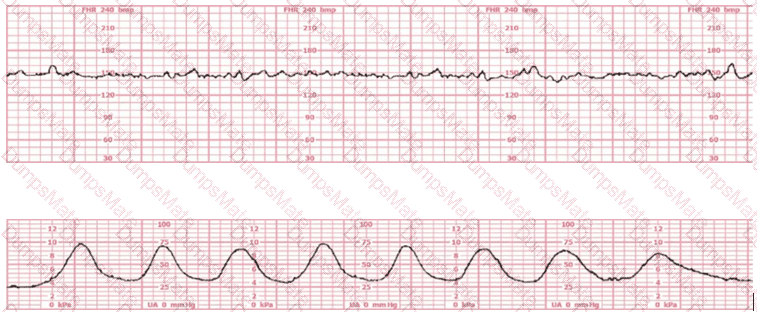

Questions 11

(Full question)

This tracing would be categorized as a

EFM Question 11

Options:

A.

Category I

B.

Category II

C.

Category III

Buy Now